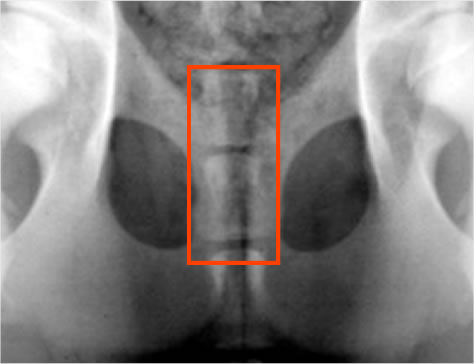

JPS(Juvenile Pubic Symphysiodesis)/ 若齢期恥骨結合固定術

股関節形成不全を発症する可能性がある幼弱犬におこなう予防的な手術。

12~18週齢で可能な手術。恥骨結合を電気的に焼灼することで骨の成長を停止させます。これにより、寛骨臼による大腿骨頭のカバーがよくなるよう骨盤の形状を変化することを期待して行う手術です。